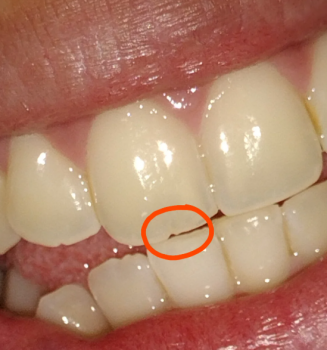

A 7-year-old male with an ectopically erupting/extruded permanent tooth (FDI 21) that presented in or near the nasal cavity/vestibule and was extracted.

Photo shows the nostril/oral vestibule area with the extraction site and adjacent mucosa — looks like soft-tissue involvement of the nose/nasal floor region rather than a simple intraoral socket alone.

Local soft tissue defect/laceration near the nasal vestibule — extraction site appears fresh.

No active heavy bleeding visible in photo (good). Mild blood clot/serous exudate likely present.

Possible communication risk between oral cavity and nasal floor depending on defect depth — needs direct clinical check.